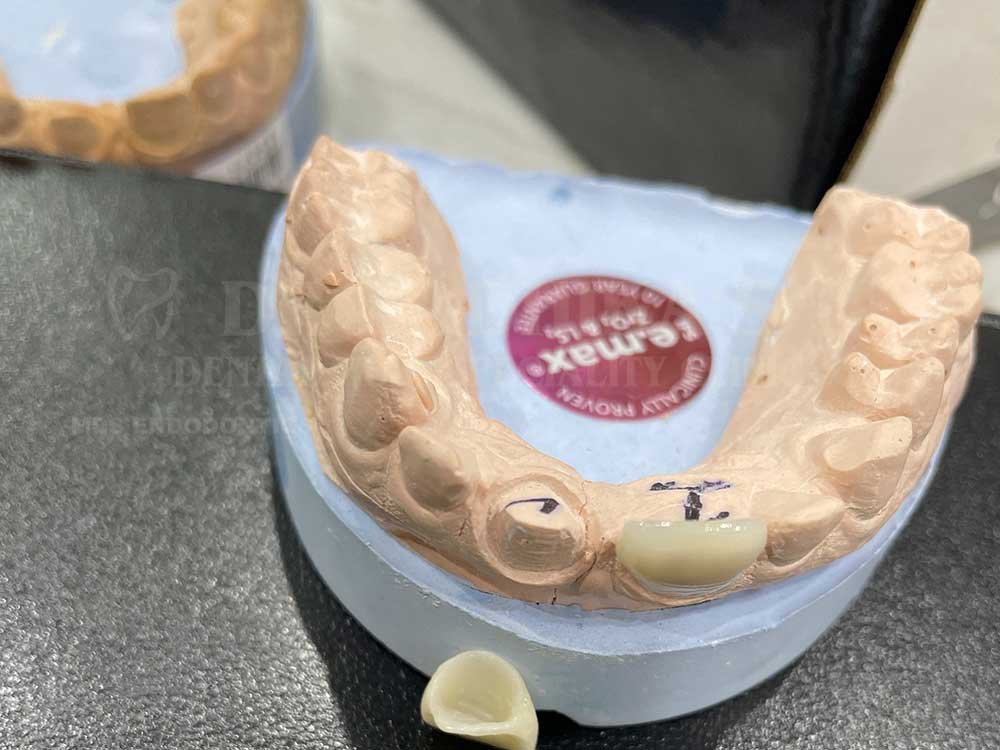

Veneers or laminates

Dental crowns or bridges

Dental veneers are ultra-thin shells made from porcelain or composite resin that are bonded to the front surface of your teeth. They are an excellent solution for correcting imperfections such as:

Porcelain veneers are highly durable and stain-resistant, making them a long-lasting solution for a radiant smile. Composite veneers, on the other hand, are more cost-effective and require minimal tooth preparation, making them ideal for quick aesthetic fixes.